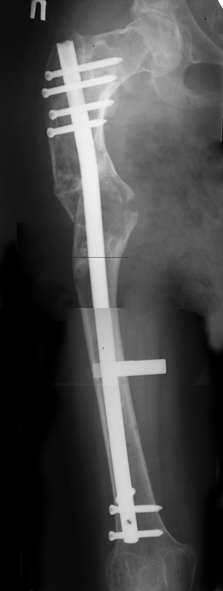

Хотелось бы показать, что получилось в результате.

Операция выполнялась с помощью А.Н.Челнокова. Очень понравилась технология выполнения блокируемого остеосинтеза с использованием спицевого дистрактора, модифицированный гвоздь с латерализованным проксимальным отделом и возможностью многовинтовой фиксации проксимального и дистального участков бедра.